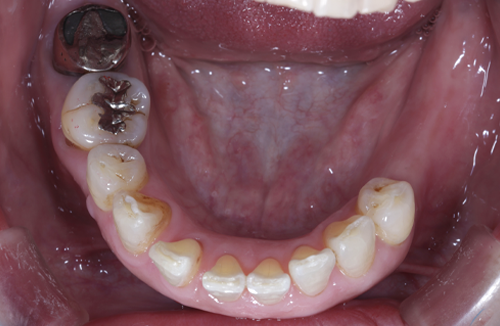

当院のインプラント治療例

― 他院で「難しい」と言われたケースにも対応 ―

※他院で骨量不足と診断された症例です。

【お悩み】

奥歯を失い、他院でインプラントの相談をしたところ「骨が足りないため難しい」と言われ、不安を感じて来院されました。

【診断】

歯科用CTにて詳しく検査を行った結果、インプラントを行うには骨量が不足している状態であることが確認されました。

【治療内容】

骨をつくる治療であるGBR(骨造成)を併用し、将来的な安定性を考慮したうえでインプラント治療を行いました。

【治療後】

現在はしっかり噛める状態となり、日常生活でも違和感なく食事を楽しんでいただいています。

【担当歯科医師からのコメント】

骨が少ないケースでも、CTによる診断と適切な治療計画によりインプラントが可能となる場合があります。

「難しいと言われた」とお悩みの方も、まずはご相談ください。